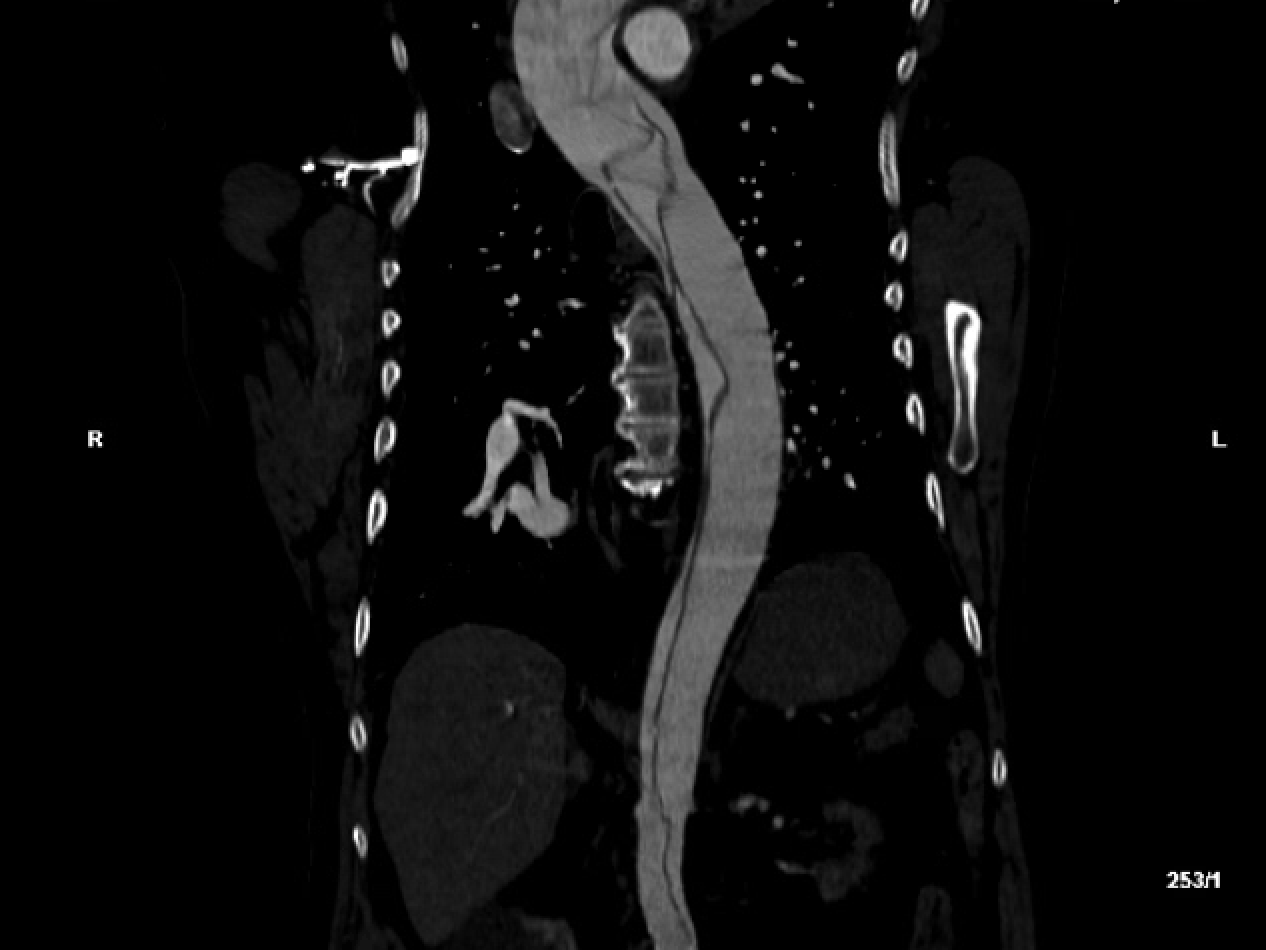

Aortic Dissection - Sagittal.png

Acute aortic dissection may present atypically, often without the classic "tearing" chest or back pain. Instead, patients may present with syncope, neurologic deficits, pulse deficits, referred pain,